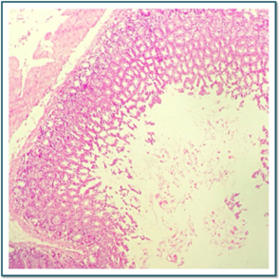

Láminas de Histología

Laboratorio de histología, Bibliografía Ross Pawlina 5ta Edición.